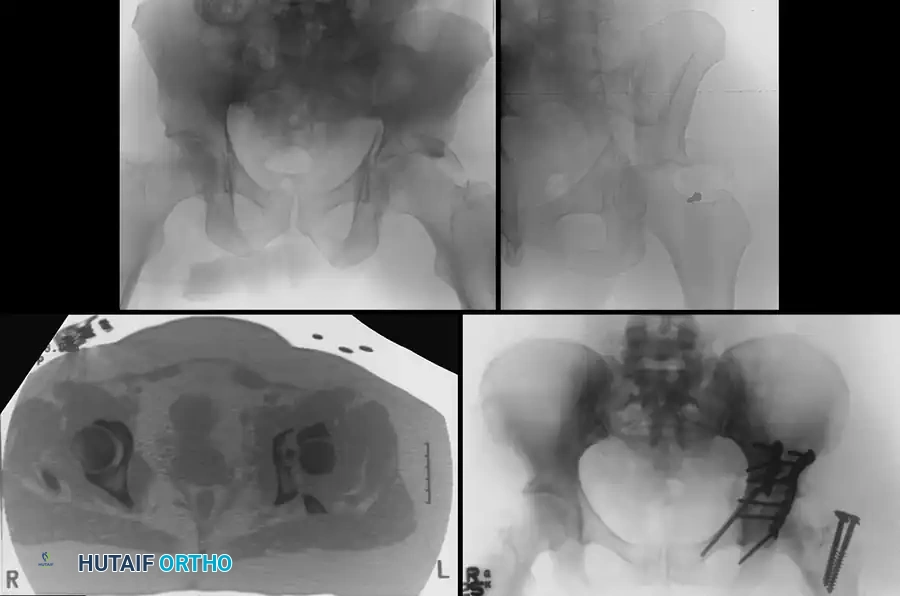

Clinical Pearl: The Spur Sign

In a both-column fracture, the intact portion of the ilium (attached to the sacroiliac joint) projects laterally relative to the medially displaced, fractured acetabular columns. On an obturator oblique radiograph, this intact bone appears as a sharp spike, known as the "Spur Sign." Its presence is pathognomonic for a both-column fracture.

Secondary Congruence in Both-Column Fractures

A unique phenomenon observed exclusively in both-column fractures is "secondary congruence." Because all articular fragments are detached from the axial skeleton, they can occasionally settle concentrically around the medially displaced femoral head.

If the articular cartilage space is preserved and the femoral head remains concentrically enveloped by the fragments (despite medialization of the entire joint complex), nonoperative treatment via skeletal traction can yield surprisingly excellent long-term functional results.